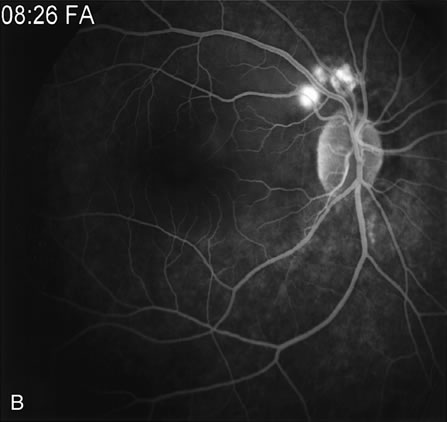

FA is also useful in characterizing two other subgroups of CNV: retinal angiomatous proliferation (RAP)8–16 and polypoidal choroidal vasculopathy (PCV).17–50 RAP begins in the deep retinal complex, forming intraretinal neovascularization (IRN), which may subsequently progress to extend beneath the neurosensory retina, forming subretinal neovascularization (SRN), and a vascularized PED.8 In the later phases of the process there may be a retinal-choroidal anastomosis (RCA). Clinical features of RAP include intraretinal hemorrhages, cystoid macular edema, and associated vascularized PED. FA is useful in revealing the presence of the angiomatous intraretinal vascular complex and the extension of the associated PED (Figs. 12 and 13). However, other diagnostic techniques such as indocyanine green (ICG) angiography, and optical coherence tomography (OCT) may be able to better demonstrate the presence of the RAP lesion.

Fig. 12. A. Clinical photograph of a retinal angiomatous proliferation (RAP) lesion (arrow). Note the intraretinal angiomatous proliferation, a feeding retinal arteriole, and a draining retinal venule, as well as the presence of intraretinal hemorrhages. B–C. Fluorescein angiography reveals late leakage from the RAP lesion.

Fig. 13. A. Early-phase Fluorescein angiography demonstrating the presence of an intraretinal angiomatous lesion (arrow). There is an associated pigment epithelium defect (PED), which is still hypofluorescent. B. Late-phase fluorescein angiography shows leakage from the retinal angiomatous proliferation (RAP) lesion and polling of dye into the PED. C. Indocyanine green angiogram of the same eye better demonstrates the presence of a hot spot corresponding to the RAP lesion. The PED remains hypofluorescent. D.Optical clearance tomography image demonstrates the presence of a serous PED and of intraretinal neovascularization.